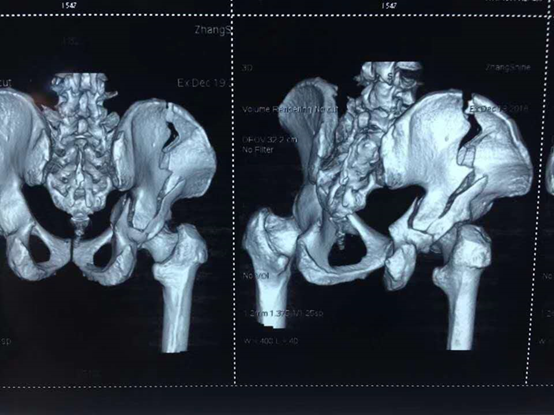

12月29日,关节外科有一骨盆右侧髋臼双柱、右髂骨骨折、右桡骨骨折合并眼球挫裂伤及全身多处软组织挫伤的患者需要做骨盆骨折内固定术,如果按照传统的体位摆放方法,需要摆两次:先仰卧位进行骨盆内侧壁切开复位内固定,缝合切口且包扎完毕后再翻转体位至侧卧位,进行骨盆外侧壁切开复位内固定。如此,则需要进行两次消毒和铺巾,这不但耗费手术时间、容易再次损伤患者而且增加手术切口感染的风险。并且,这个患者的髋臼后柱移位大,常用的前路手术不能很好的将髋臼复位,因此主刀医生邱华耀主任选择了髂脊联合KI入路,且术中需要调整患者90度侧位和60度侧位,因此需要摆放特殊体位:漂浮体位。 漂浮体位与常规体位不同,在手术室算是一个比较陌生的体位。所谓漂浮体位,即体位不用牢固固定,可根据术中需要调整患者体位。当得知要摆这一体位后,孙护士长马上过来手术间,以巡回护士黄卓筠和护士长孙灿为主导,会同手术医生和麻醉医生开始忙活起来: